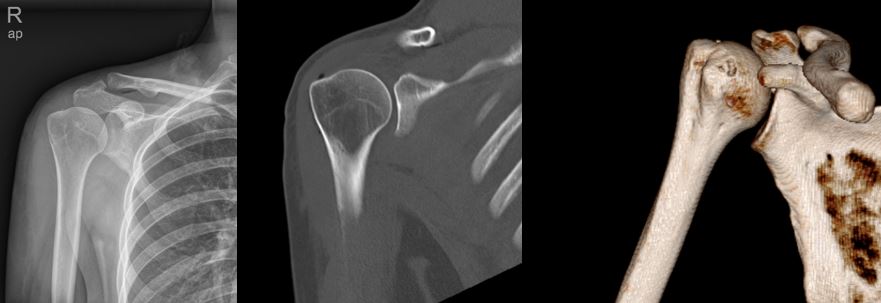

X线提示:肱骨头上方钙化灶

CT上可以看见钙化灶沉积在冈上肌腱周围

通过X线 /CT/MRI可以很容易诊断为肩袖钙化性肌腱炎,并通过关节镜微创手术,得到了根治!

手术后复查X线和CT可以可见钙化灶已经完全清理了。